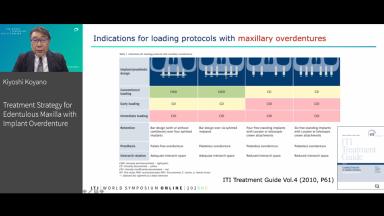

Although the success rate for implant overdentures (IOD) for the edentulous maxilla is reported as lower than for implant-supported fixed prostheses, recent studies have shown better clinical results when 4-6 implants are utilized. However, there is still a lack of clarity about the factors associated with the success of maxillary IOD, such as the number of implants, position of implants, type of attachments, splinted or unsplinted, cleanability, masticatory function, patient satisfaction, complications, long-term survival, etc. Patient factors such as bone quantity and quality, opposing dentition, bruxism, general health condition, and age should also be taken into consideration in treatment planning. This lecture will discuss these factors based on the evidence of clinical outcomes as well as patient-reported outcomes, measures and also research findings on the biomechanics of maxillary IOD.

- recognize the factors affecting the clinical success of maxillary IOD

- identify the points to be discussed in treatment planning for maxillary IOD